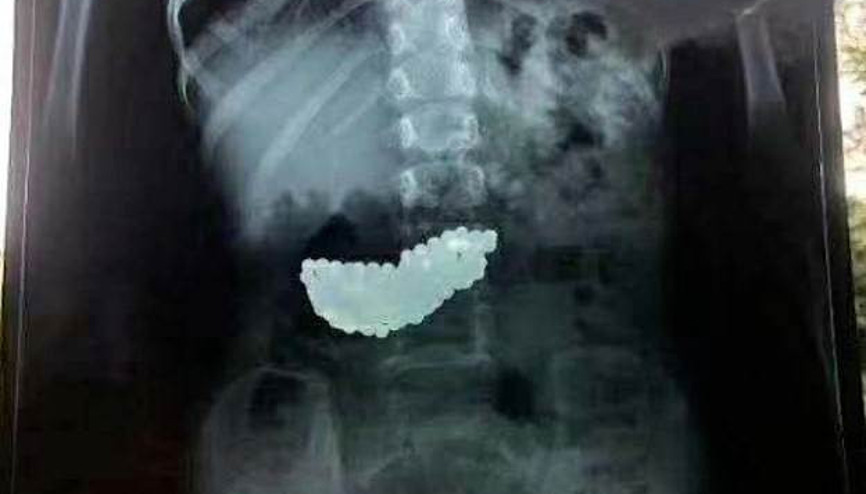

#Obeziteİstanbul'da yaşayan 4.5 yaşındaki Uras Aslan Aktaş, şiddetli karın ağrısı şikayetiyle ailesi tarafından hastaneye götürüldü. Çekilen röntgen filmi sonucu küçük çocuğun bağırsağında tam 19 tane 'neodyum mıknatıs' tespit edildi. Çocuk Cerrahisi Uzmanı Prof. Dr. Ali Çay tarafından ameliyata alınan Aktaş, sağlığına kavuştu. Prof. Dr. Çay aileleri uyararak, “Oyuncak olarak satılan bu güçlü mıknatıslar yutulduğu zaman hayatı tehdit edebilir. Ailelere bu tür oyuncaklardan uzak durmalarını öneriyorum" dedi.

#Abolfazl Sabre MokhtariBeylikdüzü’nde 9 yaşındaki çocuk oyuncak olarak satılan stres bilyeleri olarak da bilinen neodyum adlı güçlü mıknatıstan 42 adet yuttu. Kusma karın ağrısı şikayetiyle hastaneye getirilen çocuğun röntgen filmi çekilince gerçek ortaya çıktı. Ameliyata alınan çocuğun delinen bağırsağından mıknatıslar çıkarıldı.